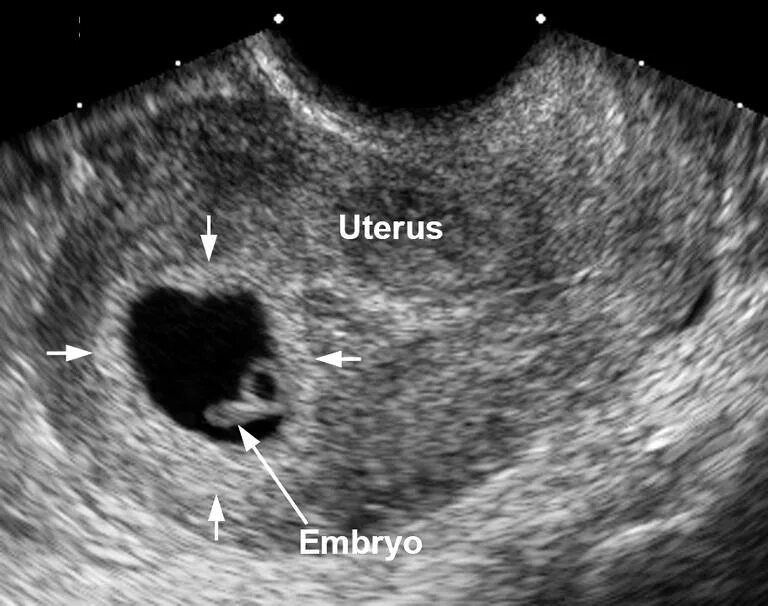

Когда можно идти на узи